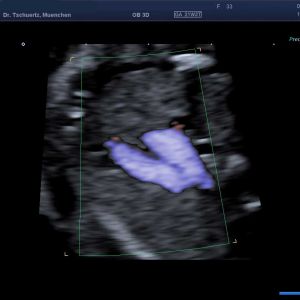

Fetale Echokardiographie – differenzierter Herzultraschall

Die Häufigkeit von angeborenen Herzfehlern beim Neugeborenen beträgt etwa 1%.

Schwerwiegende komplexe Herzfehler können schon im 1. Trimenon im Rahmen der frühen Fehlbildungsdiagnostik erfasst werden – optimaler Zeitpunkt zur Diagnostik von Herzfehlern ist die 20. - 22. SSW in Rahmen der Feindiagnostik (Organultraschall). Beurteilt werden die Lage des Herzens, die Herzkammern, die Herzklappen, die dem Herzen entspringenden Gefäße und der Herzrhythmus.

Viele Herzfehler treten in Verbindung mit Chromosomenstörungen oder syndromalen Erkrankungen auf. Wird pränatal ein Herzfehler festgestellt, bieten wir eine diagnostische Punktion zur weiterführenden genetischen Abklärung an.